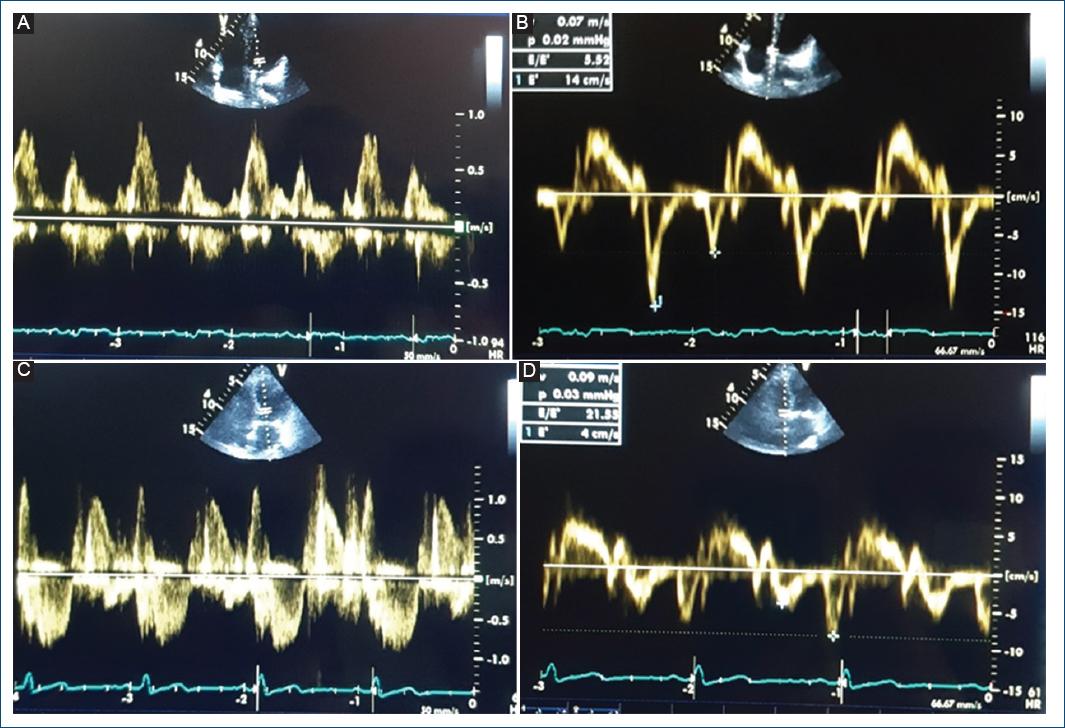

Los casos fueron adultos diagnosticados con DDVI por ecocardiografía, siguiendo las recomendaciones de la American Society of Echocardiography12. Se consideró el diagnóstico positivo cuando presentaban tres o cuatro de las siguientes características ecocardiográficas: onda e' septal < 7 m/s, onda e' lateral < 10 m/s, promedio E/e' > 14, índice de volumen de la aurícula izquierda > 34 ml/m2 (medición en dos y cuatro cámaras en vista apical) o velocidad de regurgitación tricúspidea > 2.8 m/s. Los controles fueron adultos sin DDVI confirmado por ecocardiografía. Se evaluaron otros valores ecocardiográficos, incluyendo el índice de masa ventricular izquierda determinado en modo M mediante la fórmula de Devereux según la superficie corporal, clasificado como normal según los siguientes valores: < 115 g/m2 en varones o < 95 g/m2 en mujeres. También se evaluó el grosor parietal relativo, obtenido al multiplicar el grosor de la pared media del ventrículo izquierdo por 2 y dividirlo entre el diámetro diastólico del ventrículo izquierdo, siendo considerado como normales los valores ≤ 0.42. Además, se consideró la velocidad de propagación del Doppler color en modo M como índice de función diastólica independiente de la carga ventricular, considerando como valor normal > 45 cm/s. Las imágenes características de los pacientes con o sin DDVI mediante ecocardiografía Doppler pulsado y tisular se muestran en la figura 1.

Figura 1 Imágenes características de los pacientes diagnosticados mediante ecocardiografía con Doppler pulsado y tisular. A: Doppler pulsado sin disfunción diastólica del ventrículo izquierdo. B: Doppler tisular sin disfunción diastólica del ventrículo izquierdo. C: Doppler pulsado con disfunción diastólica del ventrículo izquierdo. D: Doppler tisular con disfunción diastólica del ventrículo izquierdo.